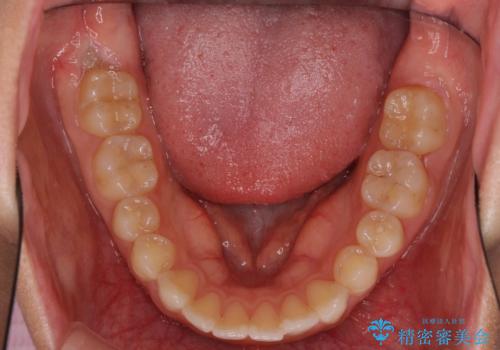

インビザライン矯正で前歯のデコボコを改善

- 前歯のデコボコを気にして来院された患者様です。

目立たないことを最優先にしたいとのことで、デコボコは軽度であったことから、インビザラインにて矯正治療を行うこととしました。

骨格的に下顎骨が左にずれており、上下の正中一致は困難ではありましたが、IPR(歯と歯の間を削る)や後方への移動など組み合わせて、できる限り改善しました。

インビザラインはマウスピースを外している時間が長いと、長期間使用しても前歯のデコボコはあまり改善されません。こちらの患者様は治療期間が長くなり、装着時間が短くなってしまったことで、気になる部分の改善により長期間を要するようになってしまいました。